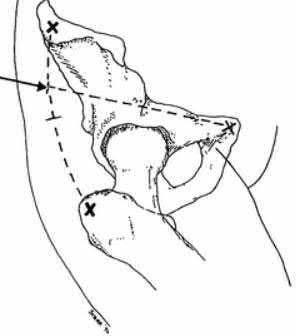

A 28-year-old male sustains a severe hyper-dorsiflexion injury to his ankle in a motor vehicle accident, resulting in a Hawkins Type III talar neck fracture. Which of the following arteries provides the predominant blood supply to the body of the talus, placing it at significant risk for avascular necrosis in this injury?

Options:

- Artery of the sinus tarsi

- Anterior tibial artery

- Dorsalis pedis

- Artery of the tarsal canal

- Peroneal artery

Correct Answer: Artery of the tarsal canal

Explanation:

The artery of the tarsal canal, which is a branch of the posterior tibial artery, provides the dominant blood supply to the talar body. In a Hawkins Type III fracture (talar neck fracture with subtalar and tibiotalar dislocation), the blood supply from the artery of the tarsal canal, the artery of the sinus tarsi, and capsular vessels are disrupted, leading to an avascular necrosis (AVN) rate approaching 100%.